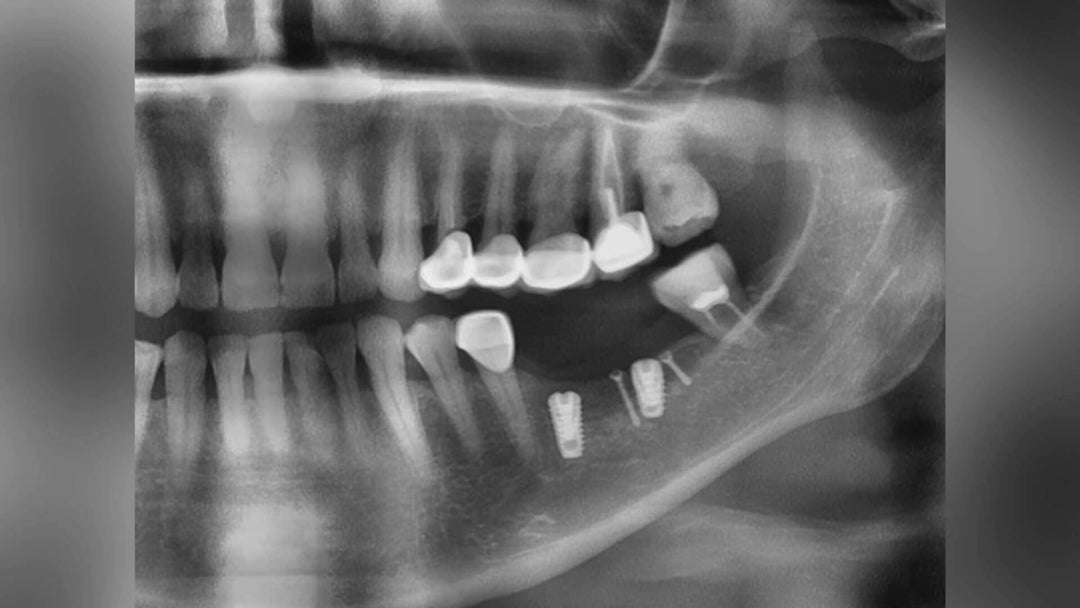

FULL MOUTH OCCLUSION RECONSTRUCTION IMPLANT CASE

In the past and even now, full mouth occlusion reconstruction has been a highly challenging process, requiring multiple visits and long-time treatment periods. The results were often not very satisfactory. However, thanks to the advancements in digital technology within the...